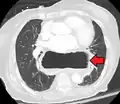

A large hiatal hernia as seen on CT imaging